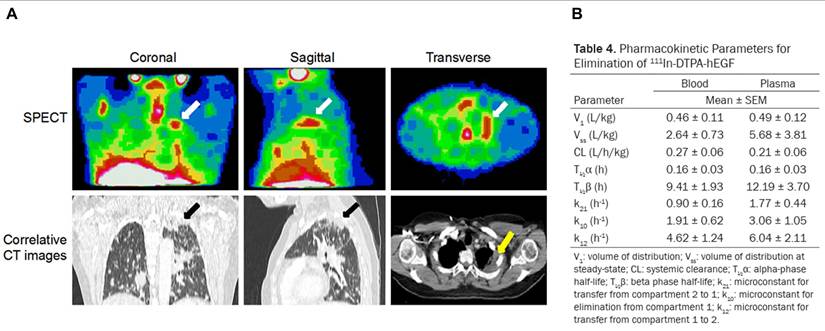

Patients with metastatic breast cancer (EGFR-positive)[111In]In-DTPA-hEGF demonstrated a favorable safety profile in a Phase I trial, with no administered activity-limiting toxicities up to 2290 MBq, rapid blood clearance, low administered activity to normal organs, and visible tumor accumulation in 47% of patients, although no objective tumor responses were observed.[22]

[111In]In-DTPA-NLS-TrastuzumabHER2Human breast cancer cell lines with HER2 positive (SK-BR-3, MDA-MB-361)Conjugation of [111In]In-DTPA-Trastuzumab with 6 NLS peptides enhanced nuclear localization in HER2-positive breast cancer cells (e.g., internalization in SK-BR-3 increased from 7.2% to 14.4%, and nuclear uptake in xenografts from 1.1% to 2.4-2.9%), resulting in up to a 6-fold increase in cytotoxicity compared with unlabeled trastuzumab and a 5-fold increase compared with [111In]In-DTPA-Trastuzumab.[115]